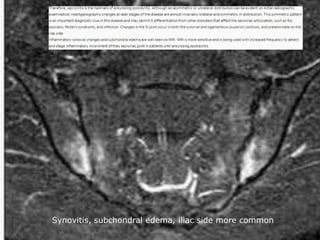

Sacroiliitis

 30 year old man with LBP HLAB27+

Synovitis, subchondral edema, iliac side more common